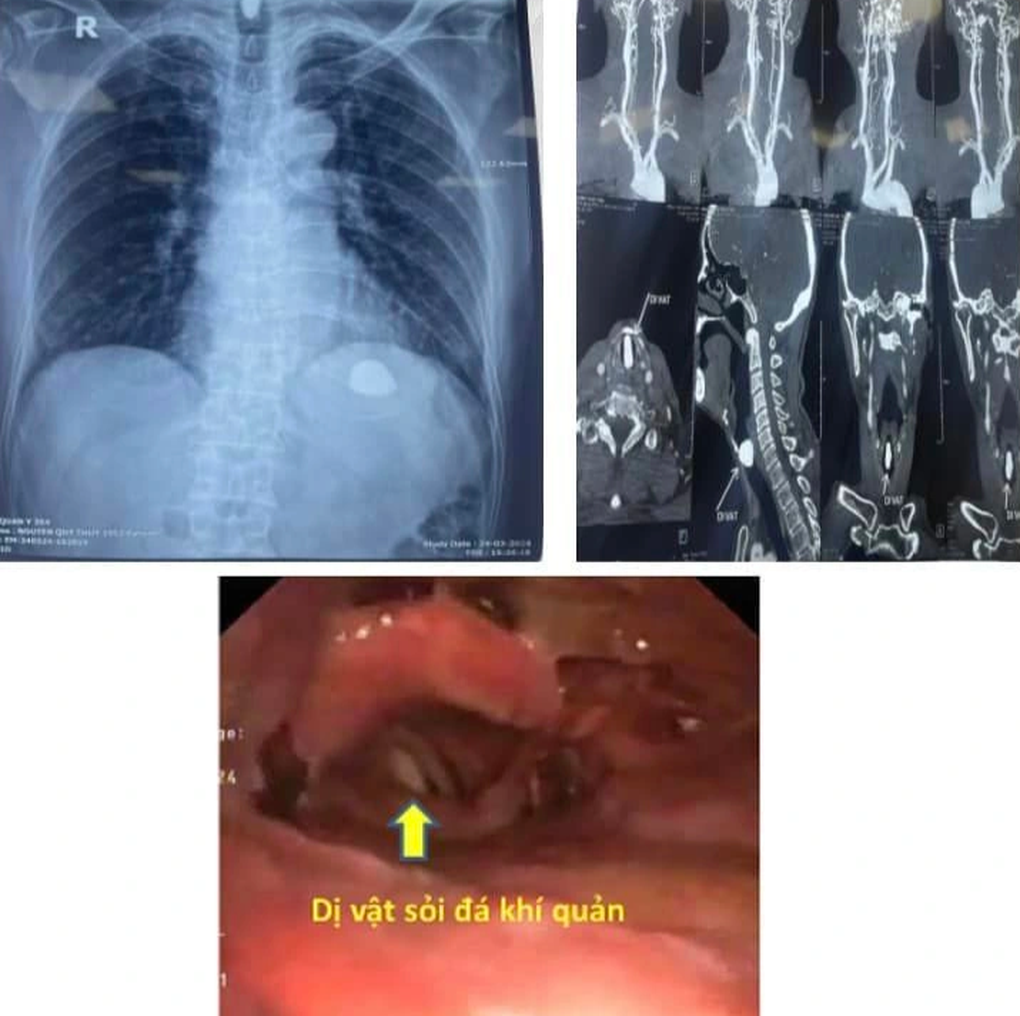

Hình ảnh dị vật là viên sỏi trắng trong đường thở người bệnh (Ảnh: Bệnh viện cung cấp).

PGS Phú cho biết, các bác sĩ đã khẩn cấp gắp dị vật là một viên sỏi thường được rắc ở giỏ hoa ra khỏi khí quản người bệnh. Ngay sau khi dị vật được lấy ra, đường thở thông thoáng, bệnh nhân không còn tình trạng suy hô hấp, đỡ khó thở nhiều, hết tiếng thở rít vùng cổ cao.

Nhiều khả năng, khi chăm các giỏ hoa treo, rắc các viên sỏi vào giỏ hoa, bệnh nhân bị 2 viên sỏi rơi vào đường thở, viên to hơn mắc ở khí quản, gây suy hô hấp.